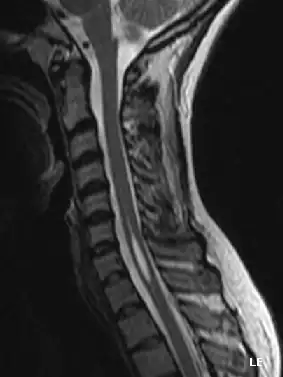

La siringomielia es un trastorno en el cual se forma un quiste dentro de la médula espinal. Este quiste se conoce como siringe o syrinx. Con el tiempo, el syrinx se expande y alarga, destruyendo el centro de la médula espinal. Puesto que la médula espinal conecta el cerebro con los nervios de las extremidades, este daño causa dolores, debilidad y rigidez en la espalda, los hombros, los brazos o las piernas. Otros síntomas pueden incluir dolores de cabeza (cefalea) y pérdida de la capacidad de sentir calor o frío extremos, especialmente en las manos. Cada paciente tiene una combinación distinta de síntomas.

Una serie de lesiones pueden obstruir el flujo normal del líquido cefalorraquídeo y redirigirlo hacia la médula espinal. Esto da lugar a la formación del syrinx o siringe, el cual se llena de líquido cefalorraquídeo. Las diferencias de presión a lo largo de la médula espinal hacen que el líquido se mueva dentro del quiste. Se cree que este movimiento continuo del líquido da lugar al crecimiento del quiste y causa daños adicionales a la médula espinal.

La mayoría de los síntomas se deben a la lesión irreversible del tejido nervioso, y este no es capaz de reemplazarlo; sin embargo, parece ser que en la siringomielia idiopática la sección del filum terminale detiene la enfermedad.[4] El quiste resultado de la necrosis celular queda igual, pero puede desaparecer cuando espontáneamente se abre el espacio que rodea la médula espinal o lo hace hacia el centro de ella donde existe un conducto, el conducto ependimario, que comunica el centro de la médula con las cavidades cerebrales.